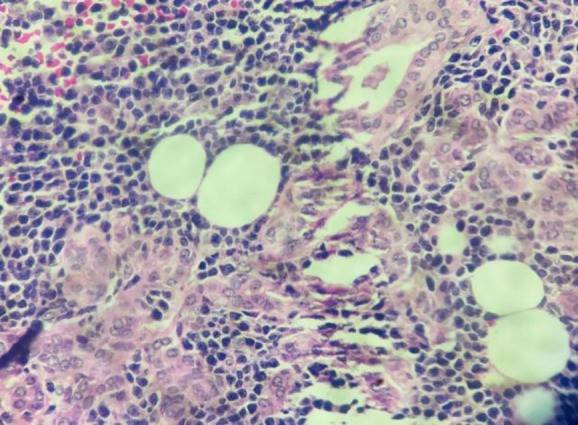

鉴于腮腺占位性病变持续存在,为明确诊断并进行治疗,患者在全身麻醉下接受了“右侧腮腺浅叶切除术”,并对右侧腮腺标本进行病理活检,提示MCL。镜下显示,正常的腮腺腺体组织被大小不一、形态单一的非典型淋巴细胞浸润——细胞核质比高,细胞核不规则、深染,染色质呈团块状,核仁不明显,胞质稀少。肿瘤细胞广泛浸润至周围脂肪及骨骼肌(图2,3)。

1111.jpg

图2. 100倍镜下(HE染色)显示腮腺组织被大量非典型淋巴细胞浸润